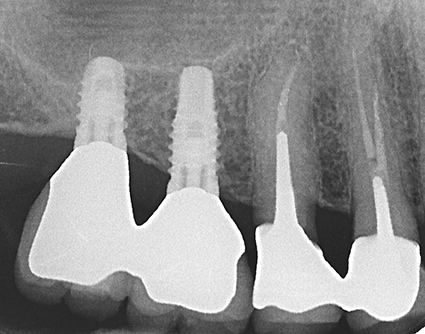

David Nisand expliquera l’approche très récente consistant à poser des implants courts dans les secteurs postérieurs résorbés.

Il démontrera, lors de cette première conférence, que le dogme suivant lequel la hauteur de la couronne clinique doit être au moins égale à la longueur de l’implant n’est pas une vérité absolue. Si cette technique ne possède pas encore le recul nécessaire, notamment dans le suivi à long terme des implants courts, la grande innovation réside dans le non-recours aux aménagements de tissus. David Nisand démontrera l’importance de l’adaptation de l’implant à l’anatomie du patient dans la pose d’implants courts.

- Pose des implants courts dans les secteurs postérieurs résorbés

par David Nisand

La plus-value tient en deux mots : nouveautés et révolutions. Les concepts, présentés par trois grands noms de la profession, sont révolutionnaires voire avant-gardistes dans le mode de la dentisterie. Pour ne donner qu’un exemple, l’intervention de David Nisand va à l’encontre des idées reçues en implantologie. Quant à Stéphane Simon et Gil Tirlet, ils repensent les techniques actuelles.